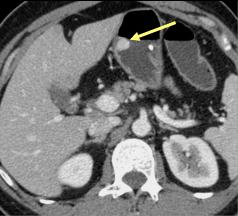

Lymphome gastrique :

Une epaississement diffuse a hypodense mais sans

stenose de l' estoma ( image TDM en coupe axiale ) .N'a

pas de rigidite a la region lesionaire |